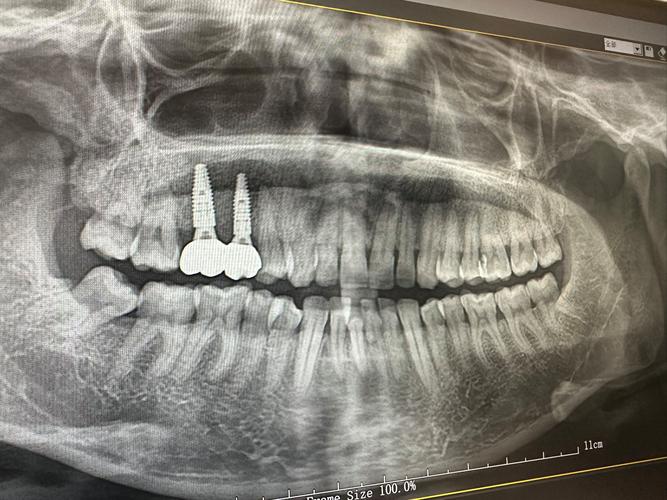

术前检查是种植成功的基础,患者需进行口腔全景片、CBCT影像检查,评估牙槽骨的高度、厚度、密度,以及邻牙和神经管的位置;同时需排查全身性疾病,如未控制的糖尿病、严重高血压、骨质疏松等,这些疾病可能影响骨结合速度,口腔卫生状况(如是否有牙周炎、牙龈炎)也需先进行治疗,确保种植环境健康。

方案设计阶段,医生会根据检查结果,结合患者的咬合关系、美学需求,制定个性化方案,对于骨量不足的患者,可能需要先进行植骨手术(如自体骨移植、骨粉填充),等待3-6个月骨结合后再进行种植;对于前牙美学区患者,还需考虑牙龈形态和牙冠颜色,以达到自然美观的效果。

手术植入是种植牙的关键步骤,在局部麻醉下,医生切开牙龈,暴露牙槽骨,使用专用种植机将种植体植入预定位置,随后缝合牙龈,手术时间通常为30分钟-2小时(根据种植数量而定),过程中患者无明显疼痛,术后需服用抗生素预防感染,7-10天拆线,期间避免食用过硬、过热食物。